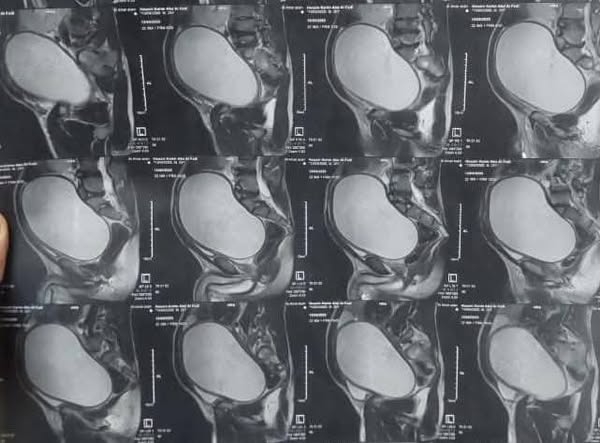

كان مستشفى جراحة المسالك قد استقبل مريض يبلغ من العمر ٢٦ عاما، ويعاني من كيس كبير يقع بين المثانة والمستقيم بأبعاد تصل إلى 12×14×18 سم، وممتد إلى منطقة البطن، وكان مصدر هذا الكيس الحويصلة المنوية، وقد تسبب ذلك في إصابته بإلتهابات متكررة، واحتباس للسائل المنوي، وكان قد تم إجراء جراحة سابقة له خارج جامعة أسيوط.

وخلال الاستكشاف الجراحي الدقيق، الذي قام به الفريق الطبي، الذي جاء برئاسة الأستاذ الدكتور أحمد الطاهر أستاذ جراحة المسالك البولية، وضم كل من، الطبيب أحمد علي استشاري جراحة المسالك البولية، والطبيب مصطفي كامل مدرس مساعد بالقسم، تبين وجود الكليتين في الناحية اليمنى من جسم المريض، بالإضافة إلى وجود عيب خلقي في الحالب الأيمن، حيث كان يفتح في كيس الحويصلة المنوية، ليتمكن  الفريق الطبي من استئصال الكيس بعد فصله بعناية فائقة عن الالتصاقات الشديدة التي كانت تربطه بالأمعاء، كما قام الفريق بإعادة زرع الحالب الأيمن في المثانة البولية بفتحة جديدة، لتستقر حالة المريض بعد ذلك.